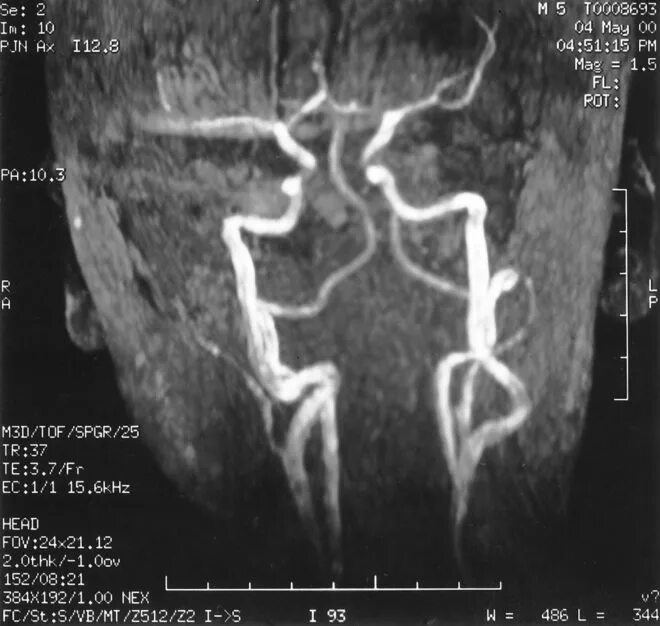

Кинкинг сонной

Кинкинг и койлинг. кинкинг внутренней сонной артерии кт. кинкинг подключичной артерии. патологическая извитость артерий (кинкинг).

Кинкинг и койлинг. извитость внутренней сонной артерии. патологическая извитость сонных артерий койлинг. кинкинг и койлинг сосудов.

Койлинг внутренней сонной артерии. извитость внутренней сонной артерии. кинкинг и койлинг. патологическая извитость сонных артерий.

Кинкинг и койлинг. кинкинг внутренней сонной артерии. патологическая извитость артерий (кинкинг). койлинг артерии.

Кинкинг и койлинг. койлинг сонной артерии. койлинг внутренней сонной артерии. извитость вса койлинг.

Извитость сонных артерий кинкинг. патологическая извитость сосудов шеи. извитость внутренней сонной артерии. извитость сифонов внутренних сонных артерий.

Кинкинг вса. патологическая извитость артерий (кинкинг). извитость сонных артерий кинкинг. кинкинг синдром внутренних сонных артерий.

Кинкинг и койлинг. патологическая извитость артерий (кинкинг). патологическая извитость сонных артерий койлинг. s-образная извитость внутренней сонной артерии.